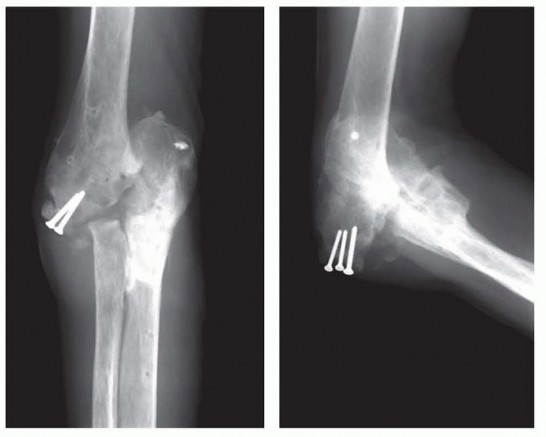

Surgical Management of Traumatic Conditions of the Elbow: Interposition Arthroplasty